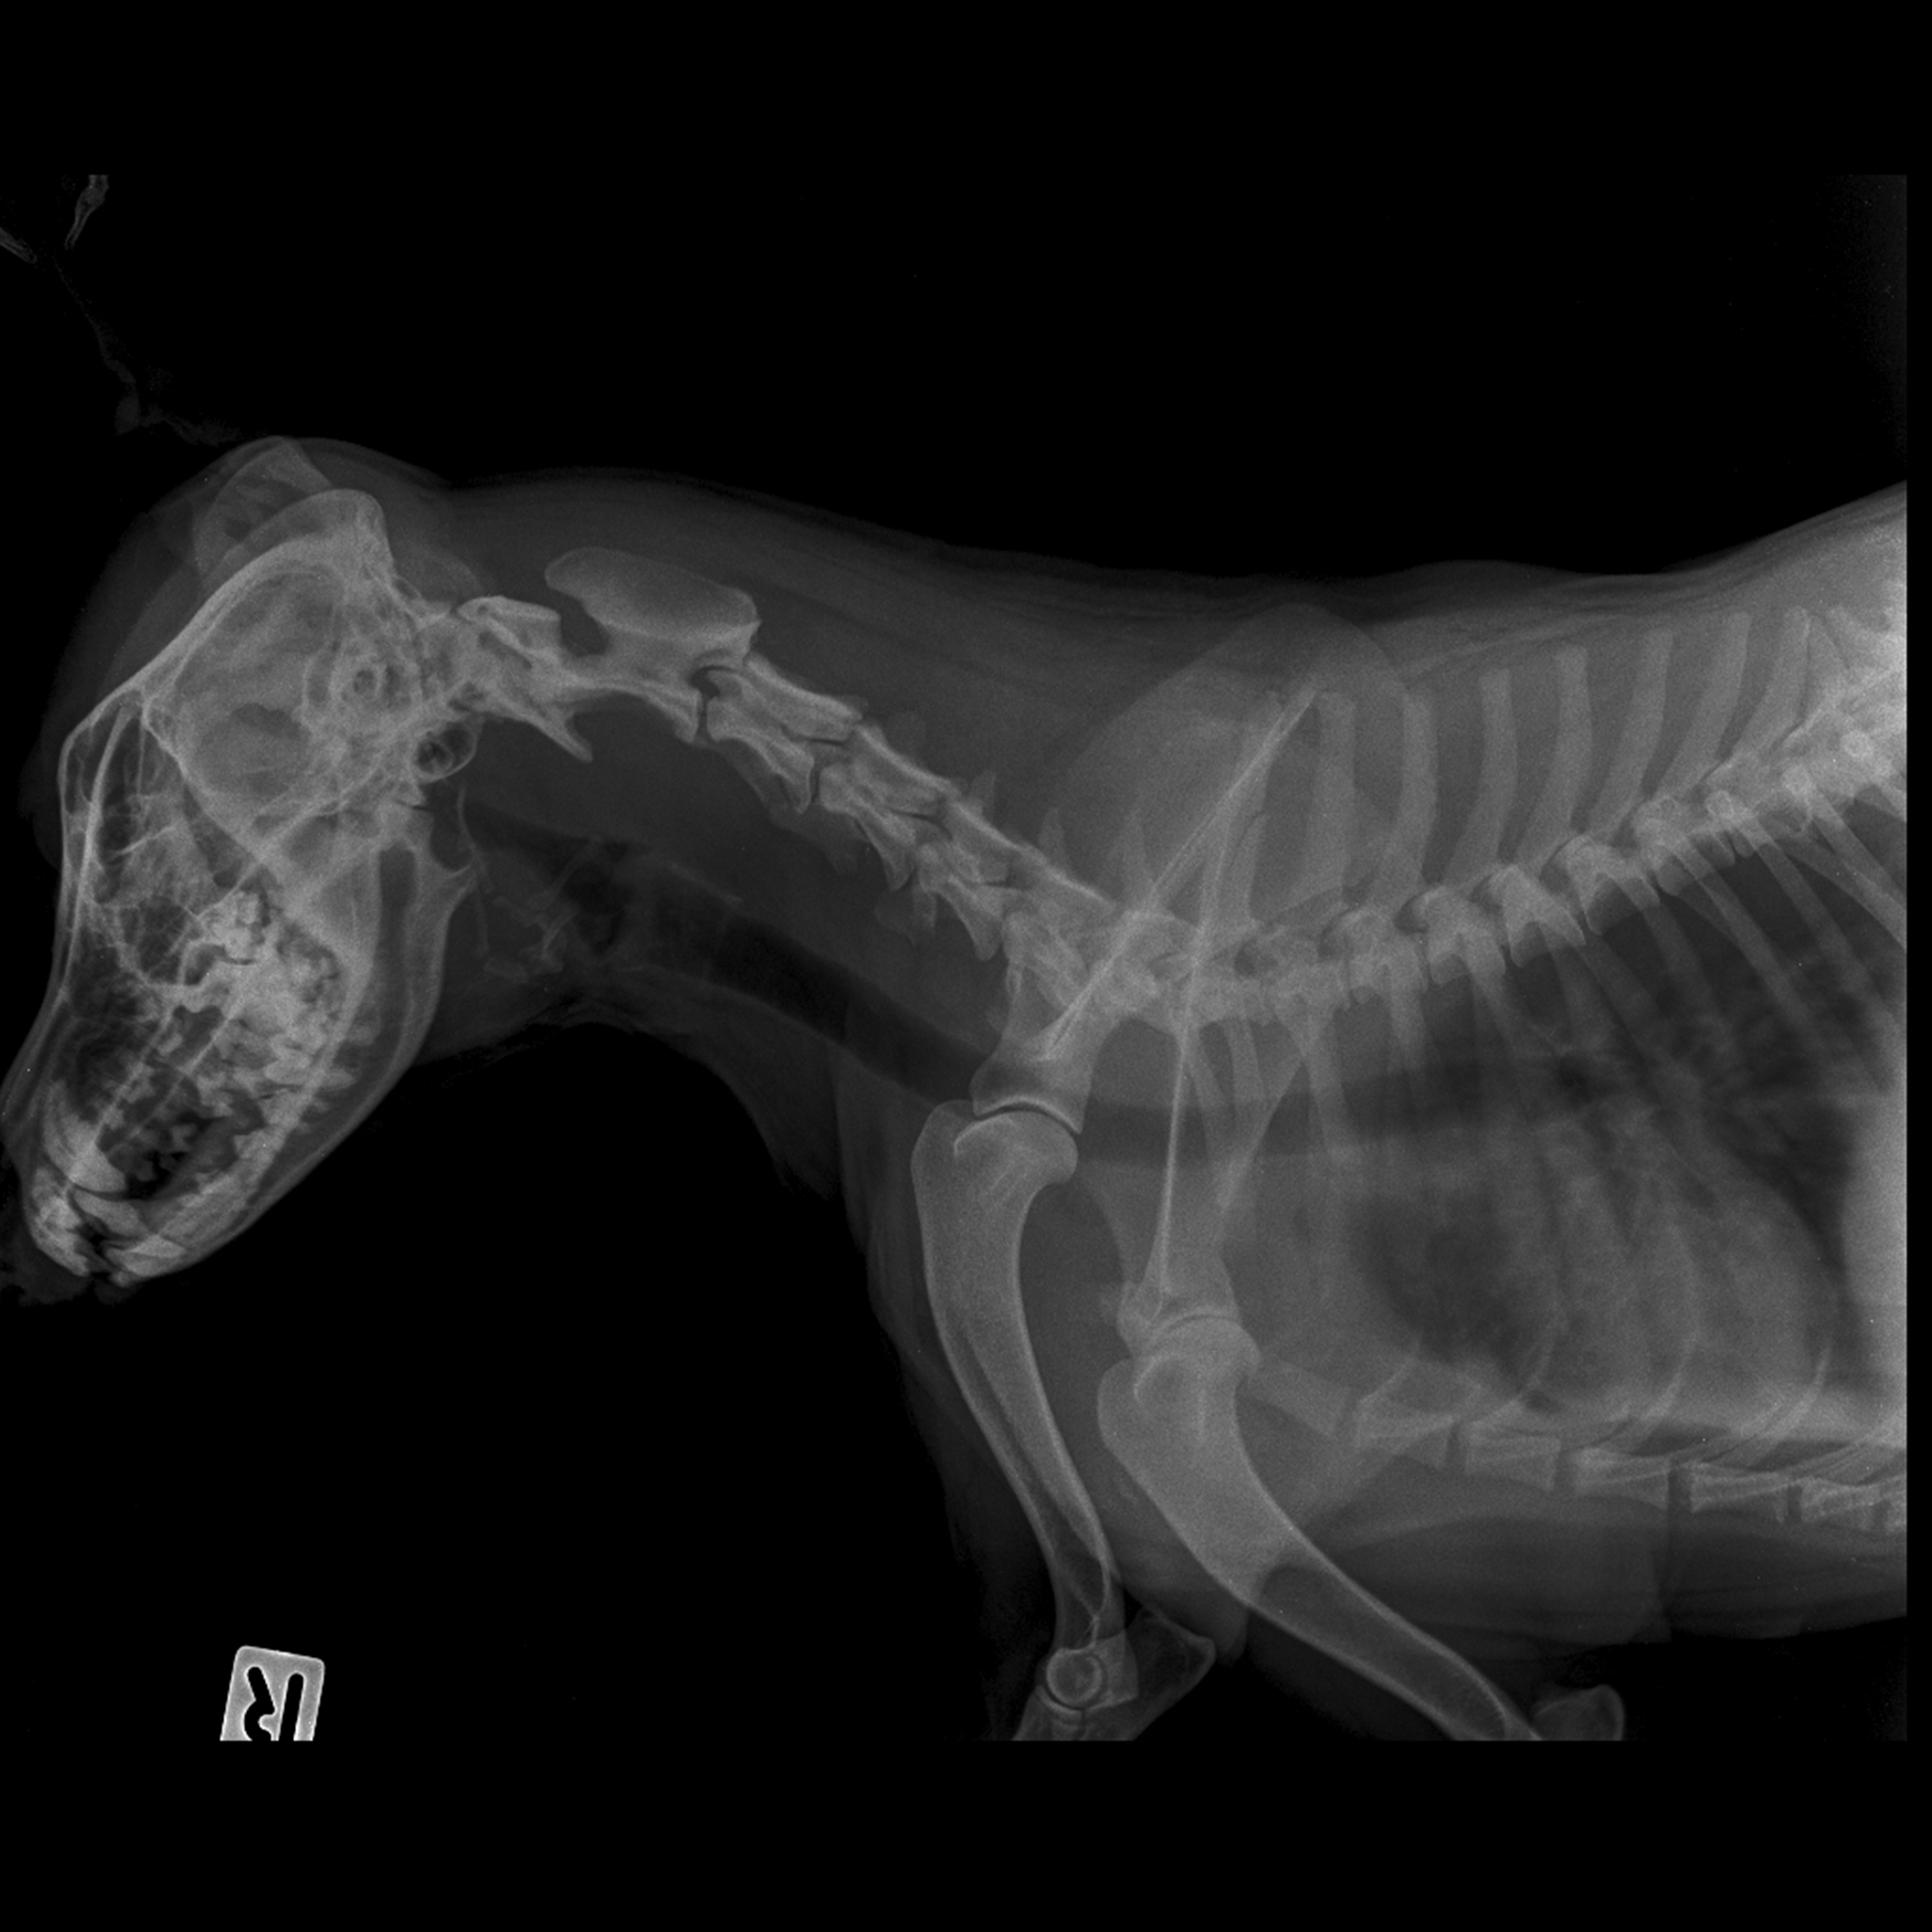

The test can be performed by a licensed veterinarian, and requires an x-ray of both the cervical and thoracic areas of the trachea. X-rays should be taken when the patient is awake and at peak inspiration.

A Board Certified Radiologist will review the x-rays, subjectively evaluating tracheal size and uniformity. They also provide an objective evaluation based on the ratio (TLR) of the tracheal lumen diameter at the thoracic inlet to the width of the proximal third rib.

If dogs are at least 12 months of age, have a normal evaluation of the tracheal size and uniformity, and a TLR greater than or equal to 2.0, they can receive an OFA certification and number. Indeterminate cases will be reported as equivocal, and abnormal cases will be reported as hypoplastic.